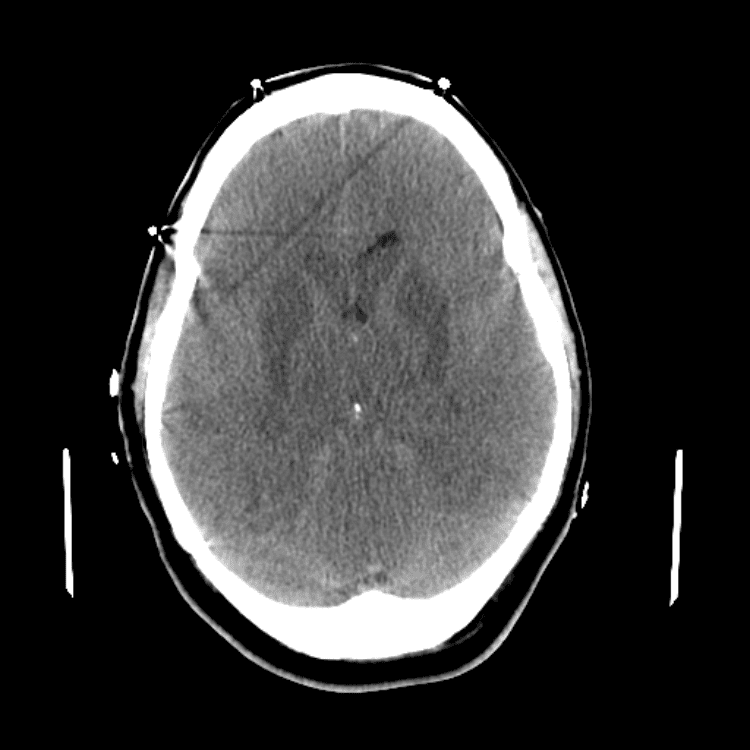

Practice

Simulates call by including subtle or difficult cases and some normals.